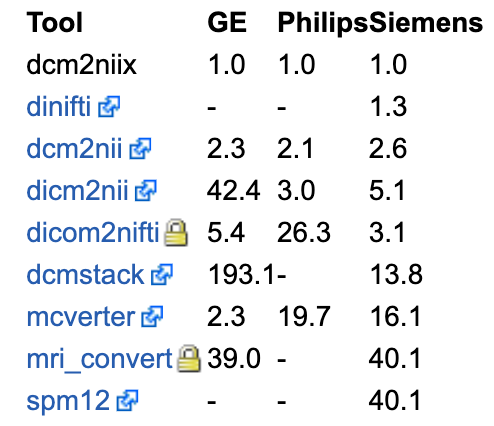

以下是不同工具处理数据所需花费的时间。dcm2niix为对照组,表里的时间是相对dcm2niix而言的